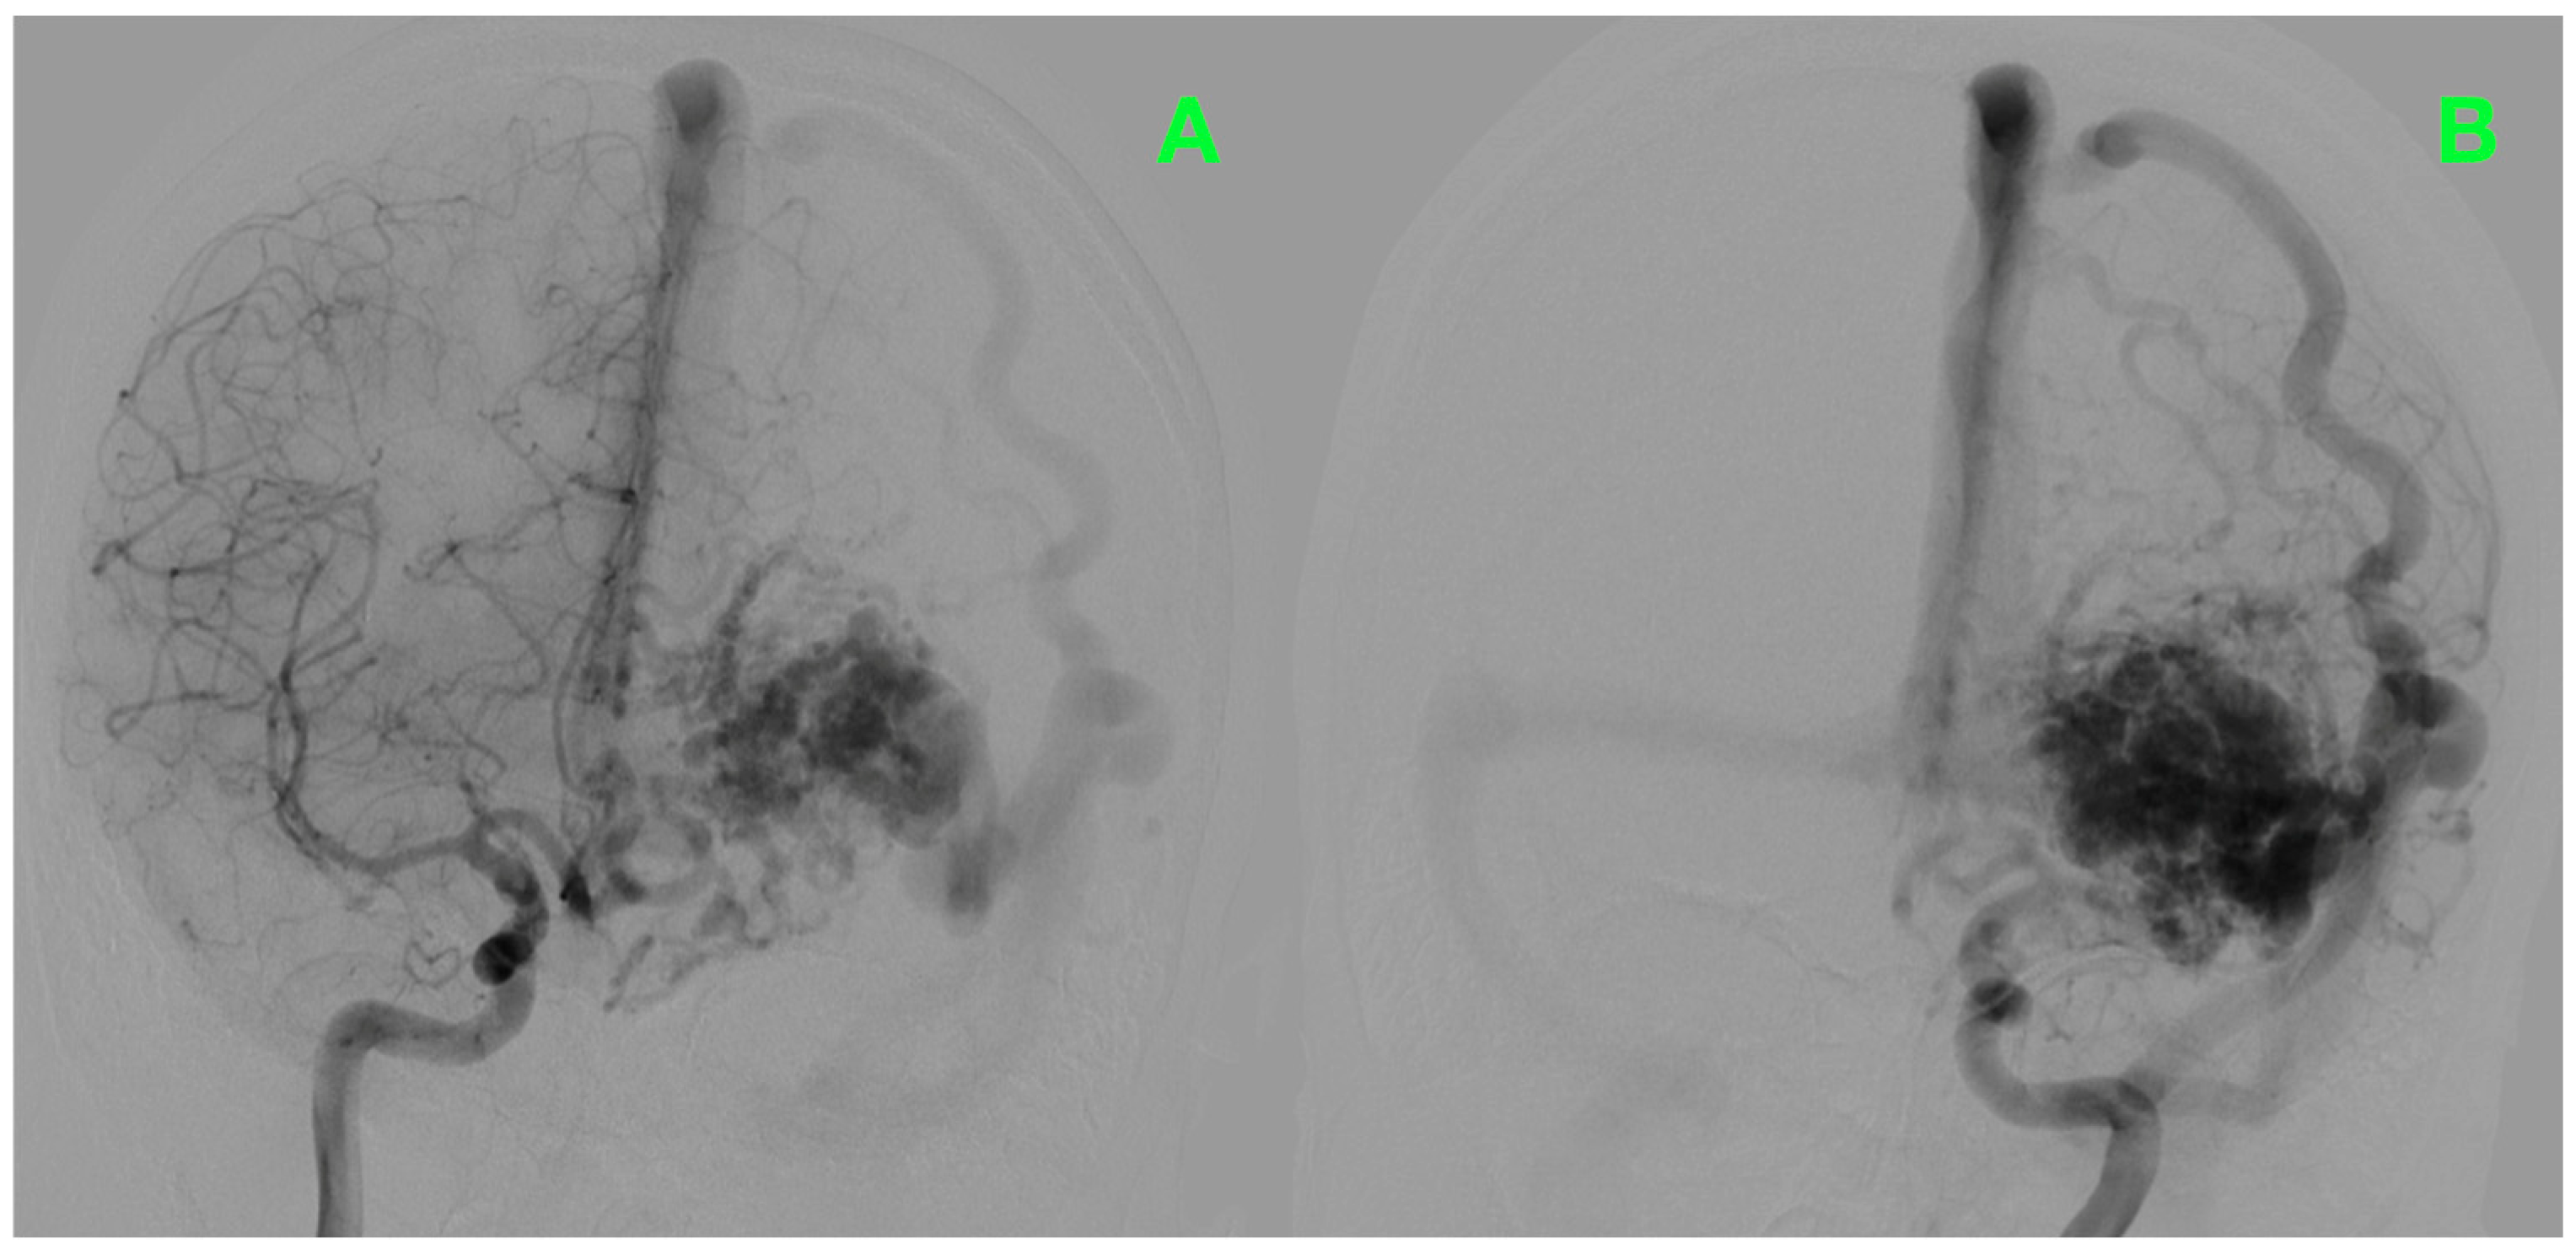

2.2. Diagnostic Workup

2.4. Surgical Intervention